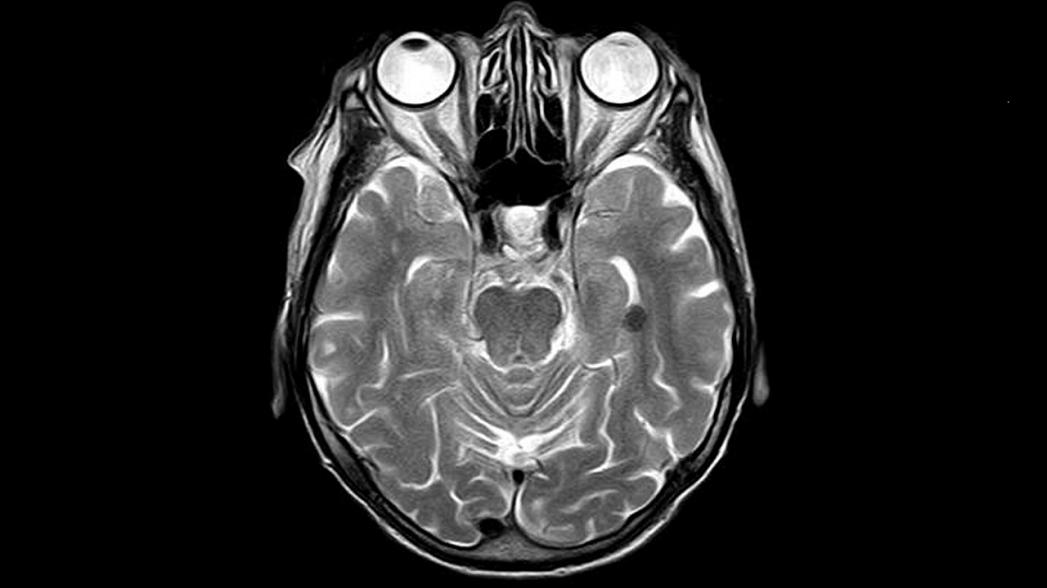

Сканер легко перевозит на тележке один человек. При дальнейшей доработке и замене стандартных компонентов оборудования на более легкие, изготовленные по индивидуальному заказу, по мнению разработчиков, вес возможно уменьшить до 160 килограммов. В ходе тестирования на трех здоровых взрослых добровольцах сканер смог успешно сгенерировать трехмерные изображения мозга. В среднем на это уходило 10 минут.